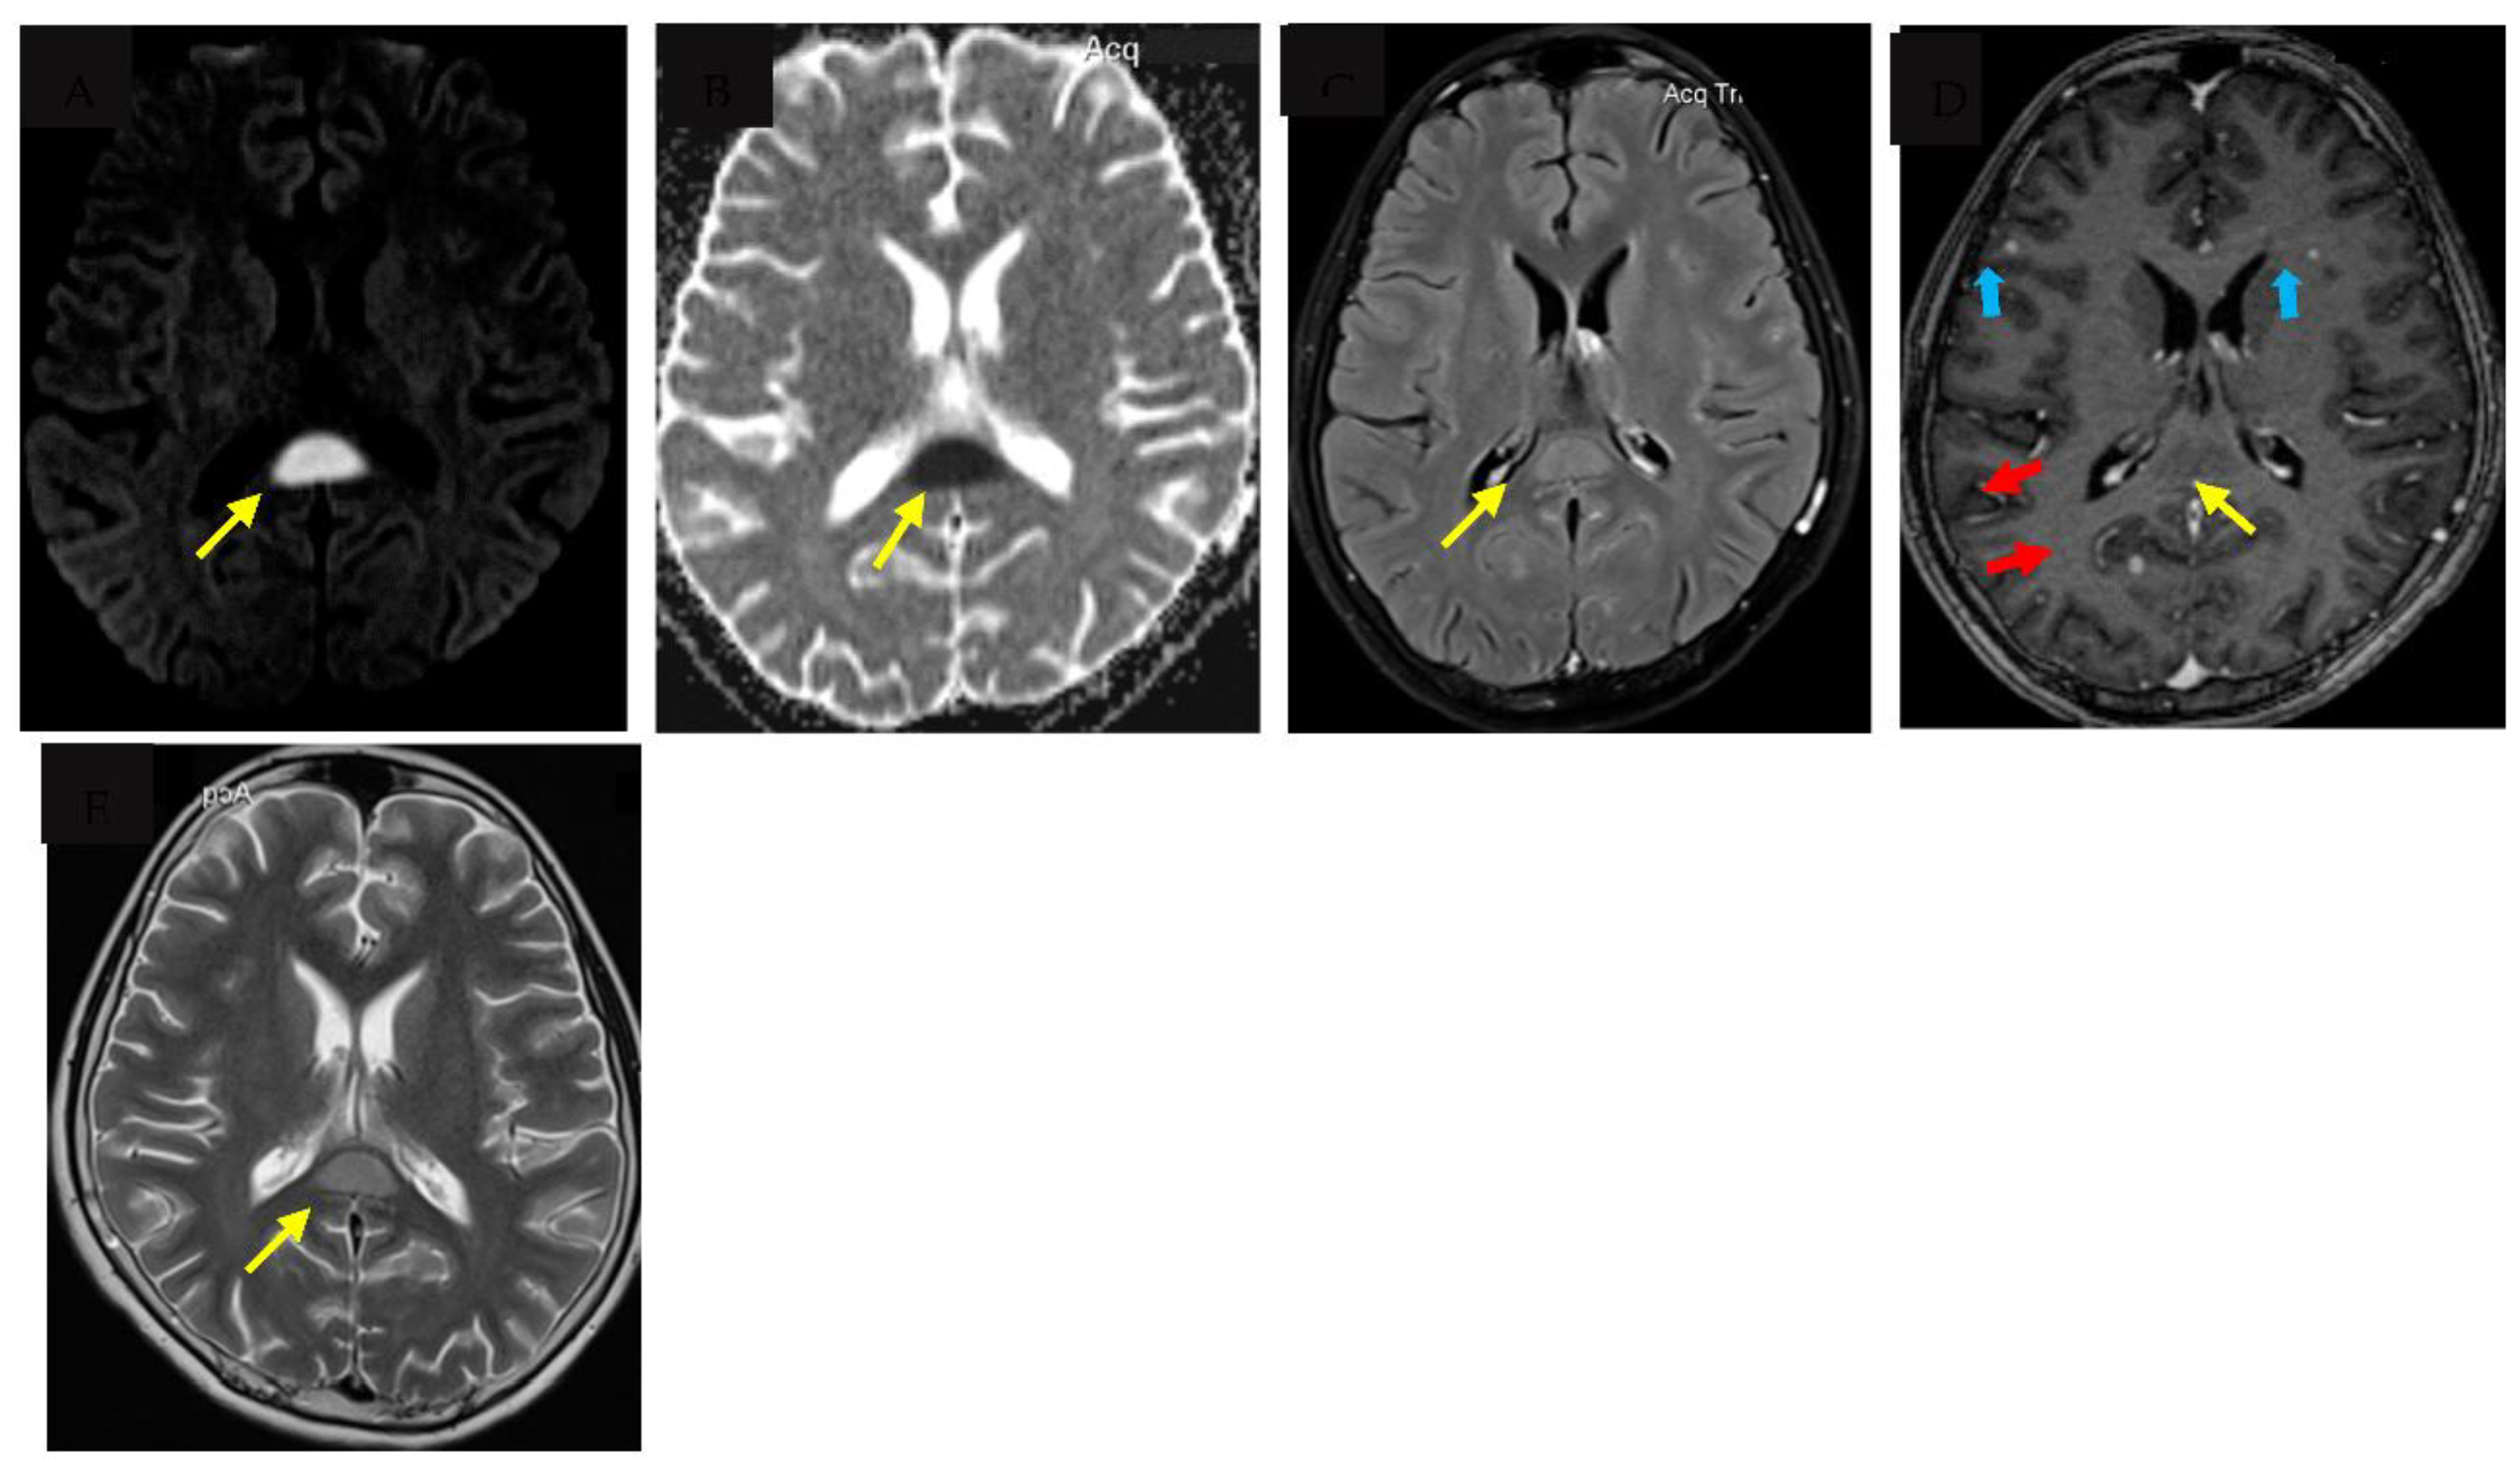

Tuberculous meningitis (TBM) is the most severe form of tuberculosis, disproportionately affecting vulnerable populations such as young children and people living with human immunodeficiency virus (HIV). Major challenges to accurate and early diagnosis of TBM are the non-specific clinical features which overlap with other infectious syndromes and the lack of adequately sensitive tests to detect Mycobacterium Tuberculosis in the cerebrospinal fluid (CSF). Diagnosis is therefore still dependent on clinical suspicion along with clinical features, cerebrospinal fluid (CSF) characteristics and where facilities are available, neuroimaging. Typical neuroimaging features of TBM include hydrocephalus, infarcts, tuberculomas and basal exudates, however less well described are very rare features such as cytotoxic lesion of the corpus callosum (CLOCC) otherwise known as transient splenic lesion. We describe the first case report of a child with confirmed TBM who had a very rare presentation of CLOCC, present a literature review on the pathophysiology and alternative aetiologies where CLOCC is more commonly seen.